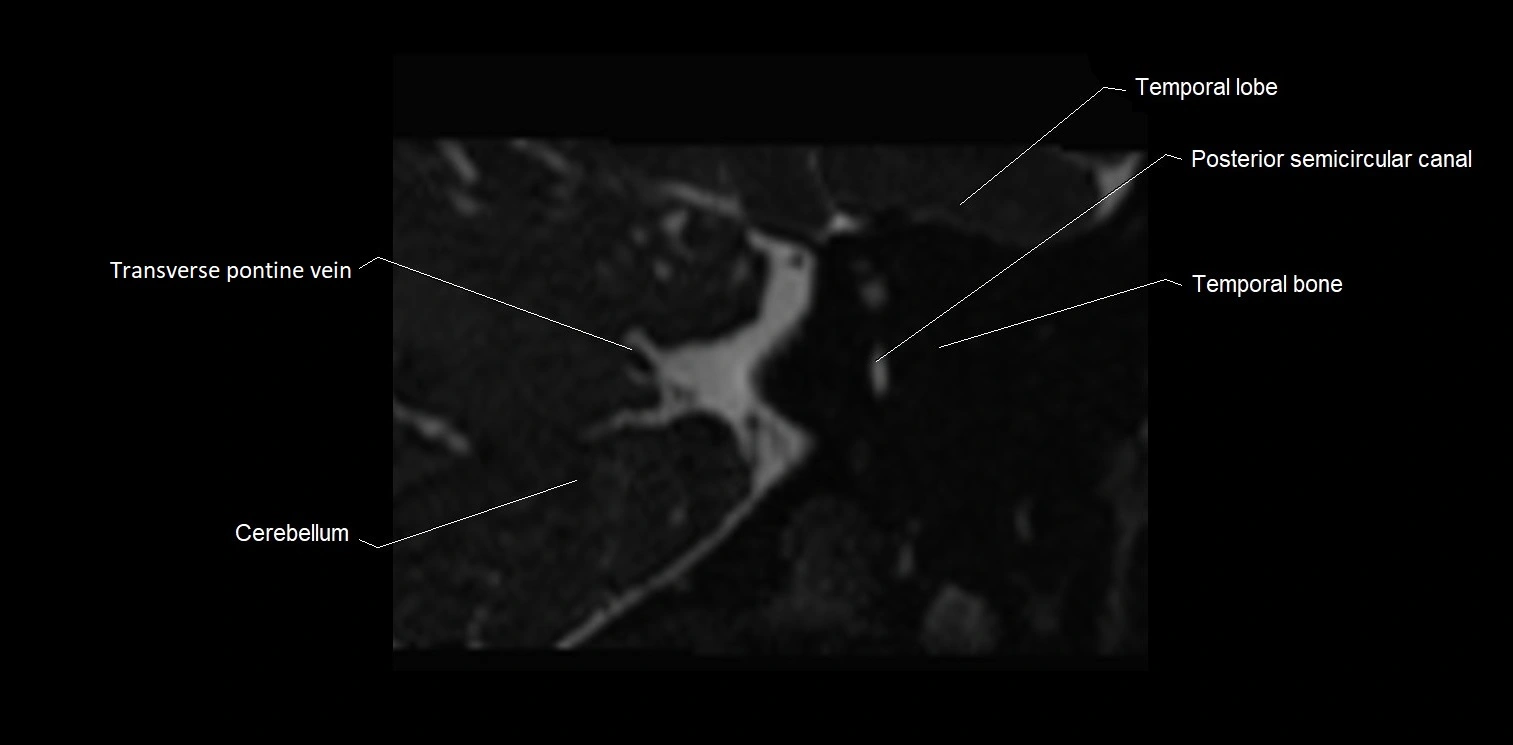

MRI Appearance

• The abducens nerve is a small, thin, linear structure

• Best visualized on high-resolution T2-weighted 3D MRI sequences (e.g., FIESTA or CISS)

• Seen as a hypointense (dark) line running from the brainstem at the pontomedullary junction, traversing the prepontine cistern, and entering Dorello’s canal under the petrosphenoidal ligament, then into the cavernous sinus, and finally the orbit

• May be challenging to visualize in standard MRI due to its small size

• Pathology may be inferred by absence, displacement, or enhancement of the nerve